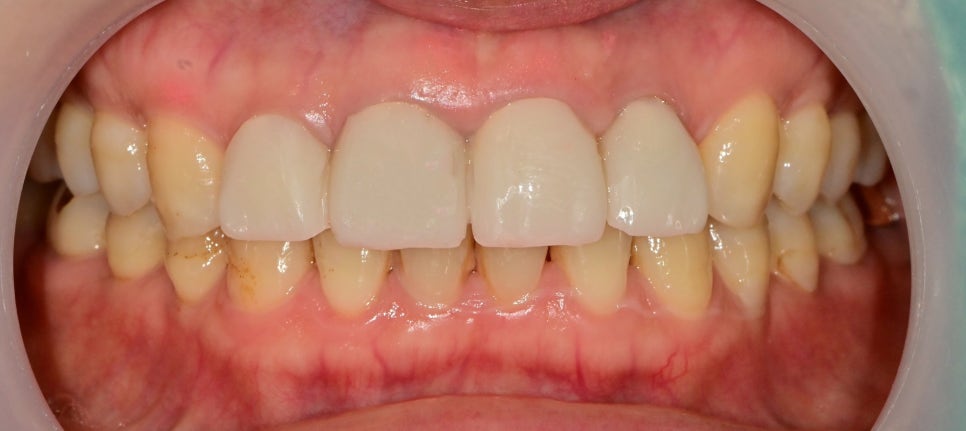

임시치아 상태에서의 비율, 형태의 평가

기존 치아의 형태가 너무 짧아 비율적으로 안 맞았기 때문에

임시치아 상태에서는 치아 길이를 조금 연장해서 형태를 잡아보았습니다.

아직 임시치아 상태이고 수정을 여러 번 하며 환자분께서는

현상태의 치아 형태가 가장 마음에 들어 하셔서 임시치아의 형태를 참고하여 최종 보철물을 제작하기로 했습니다.